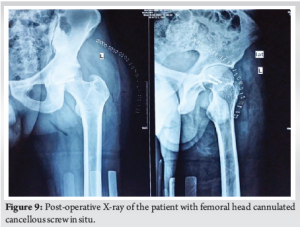

On 10th day post-trauma, the patient positioned in right lateral position, using Kocher-Langenbeck approach, the patient underwent left head of femur open reduction internal fixation with 2 headless compression screws, and posterior acetabular wall fracture was reconstructed using Ethibond. The choice of a posterior approach was chosen in view of initial presentation following injury being posterior, the tear of the capsular and muscular structures allows direct access to the joint and following fixation, and the torn structures can be visualized and repaired. The only limitation of achieving absolute reduction is to deliver the remaining portion of the infrafoveal femoral head to the rest of the femoral head and proximal femur, thereby gaining the necessary trajectory for screw fixation. This was achieved by dislocating the femur and accessing the infrafoveal fragment through the inferior portion of the joint and then reducing the fracture with a reduction clamp and provisional fixation was done with two 2 mm Kirschner wires, following which headless compression screw was inserted and maximum compression was achieved in-between the fragments (Fig. 8). The hip was relocated, the capsule was repaired with Ethibond, and the torn external rotators were reconstructed. Using image intensifier, it was confirmed that the joint was congruous; clinical assessment under anesthesia was performed and there was no impedance or blockade throughout the complete range of movements in all planes. To reduce the morbidity and the risk of arthrofibrosis of the knee, PCL reconstruction was planned for at a later date. Post-operative X-ray was done on post-operative day 2 which showed excellent reduction and articular congruity (Fig. 9).